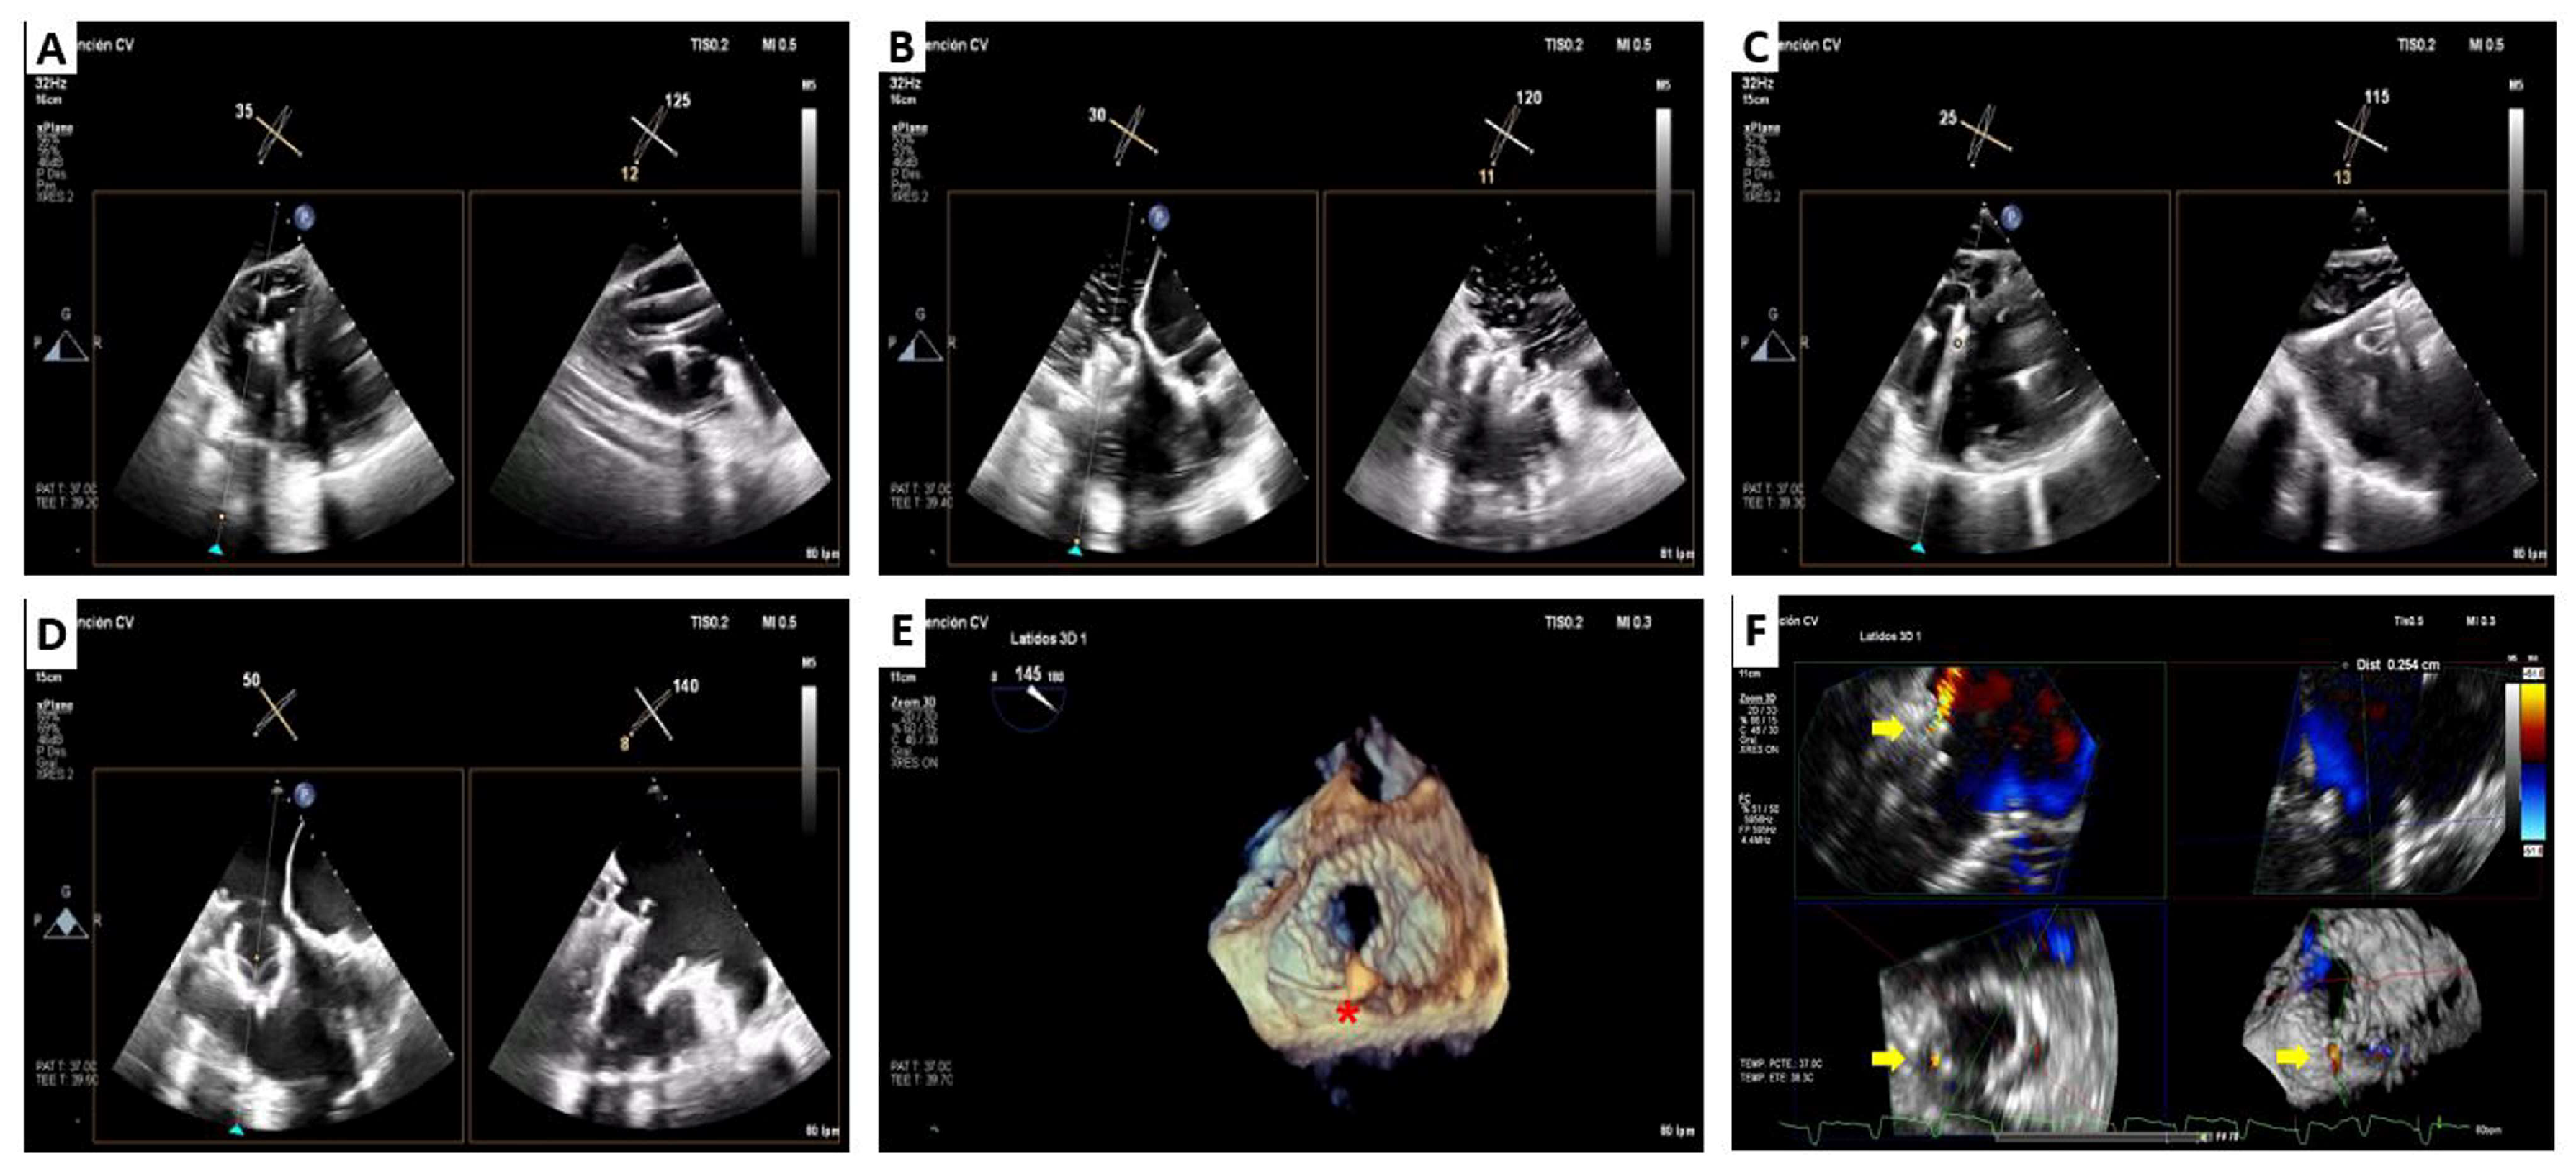

2. Cardiovalve Cases

4.2. Cardiovalve